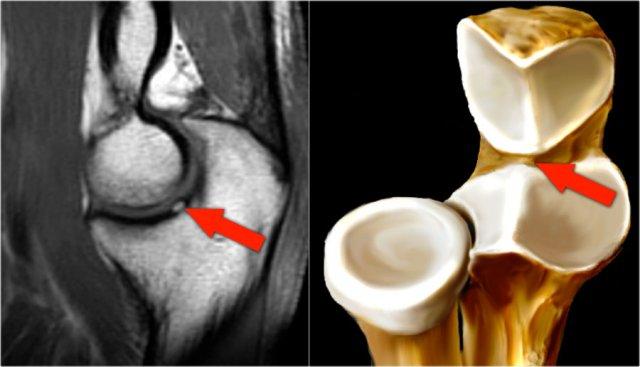

Pseudodefect of the capitellum

Đây là một phát hiện mà bạn thường thấy trên các hình ảnh mặt phẳng coronal.

Trông có vẻ giống như một tổn thương sụn xương, nhưng nếu bạn nhìn vào hình ảnh mặt phẳng sagittal, bạn sẽ nhận thấy rằng hình ảnh mặt phẳng coronal đi qua phần không có khớp phía sau của chỏm con.

Vì vậy, khi khuỷu tay duỗi hoàn toàn, một phần của chỏm quay thực sự nằm phía sau bề mặt sụn khớp của chỏm con.

Trên hình ảnh mặt phẳng coronal, chúng ta sẽ quan sát thấy chỏm quay được bao phủ bởi sụn và đối diện với nó là phần không được bao phủ bởi sụn của chỏm con, phần này thường có phần không đều.